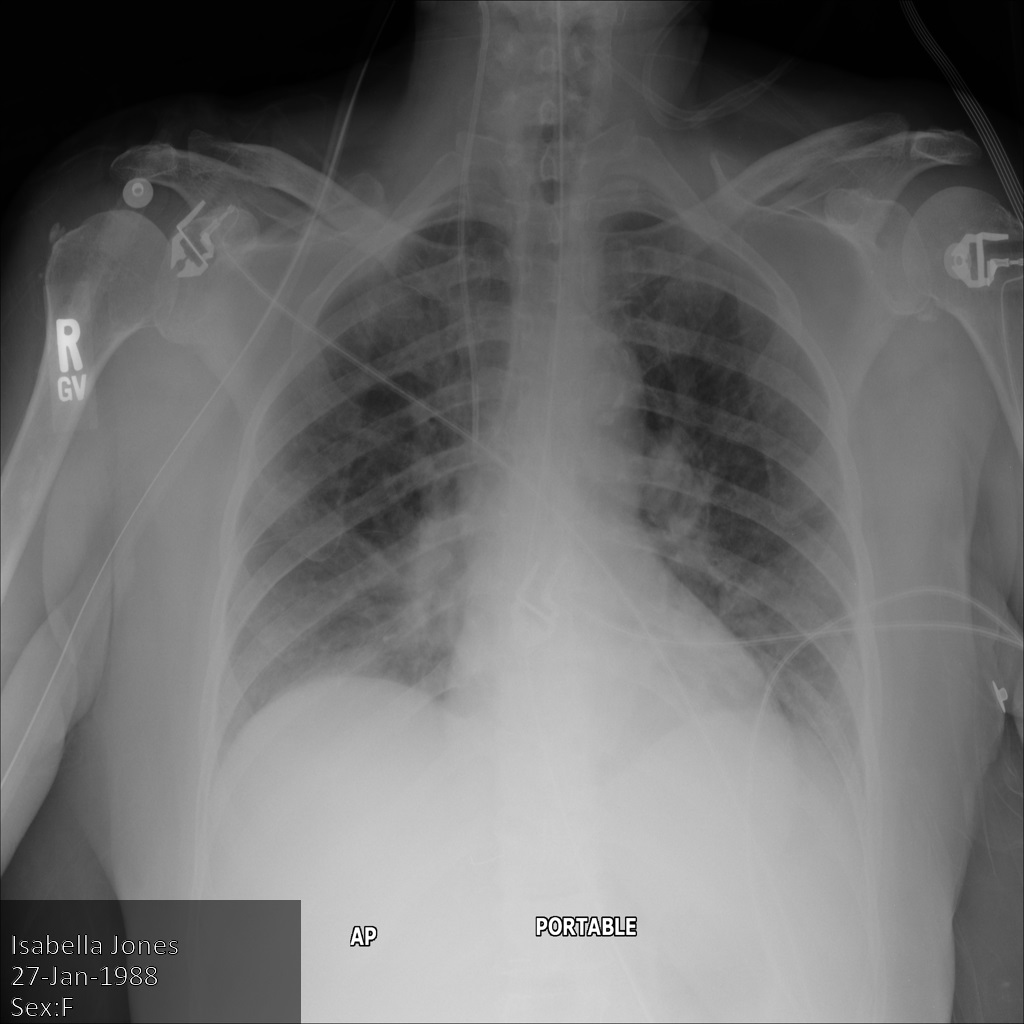

下图显示了未经遮盖的患者 X 光片:

使用 REDACT_SENSITIVE_TEXT 选项将图片提交到 Cloud Healthcare API 后,图片显示如下:

您可以看到以下情况:

- 图片左下方的

PERSON_NAME已被遮盖 - 图片左下方的

DATE已被遮盖

根据默认 DICOM infoType,该患者的性别不属于敏感文本,因此未遮盖。